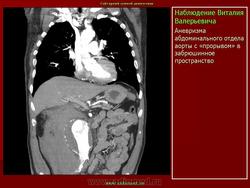

Наблюдение Tatarin